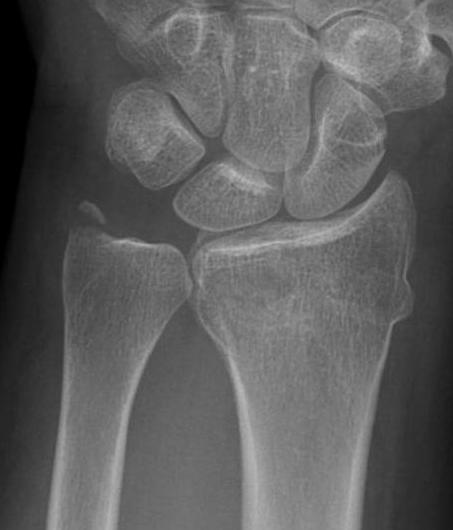

Isolated dorsal dislocation DRUJ

Isolated dorsal DRUJ instability with ulna sided TFCC tear

Xray

True lateral

- radial styloid overlies proximal scaphoid / lunate / triquetram

Dorsal subluxation of the distal ulna